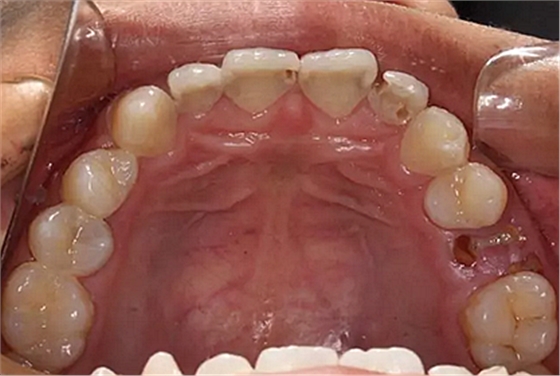

我們的主人今年才25歲,可卻從很小的時(shí)候就嗜好喝可樂等碳酸飲料,幾年下來,讓我們兄弟姐妹們整天浸在碳酸里受這蝕骨之痛,原本皎潔的外貌如今早己經(jīng)是腐蝕不堪、丑陋無(wú)比,更有甚者,一些兄弟姐妹們已經(jīng)病入膏肓,被病痛折磨奄奄一息。

下面是醫(yī)生眼中和ct下的我們

一身病痛啊

牙結(jié)石、牙齦炎癥、牙體殘缺、慢性牙髓炎、蛀牙......

才二八芳華的我們

已經(jīng)滿目蒼夷

再來看看曾經(jīng)的我們